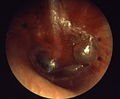

Otorrhea: infected drainage from the middle ear

When the middle ear becomes acutely infected by bacteria, pressure builds up behind the ear drum, usually but not always causing pain. In severe or untreated cases, the tympanic membrane may rupture, allowing the pus in the middle ear space to drain into the ear canal. If there is enough of it, this drainage may be obvious. Even though the rupture of the tympanic membrane suggests a traumatic process, it is almost always associated with the dramatic relief of pressure and pain. In a simple case of acute otitis media in an otherwise healthy person, the body’s defenses are likely to resolve the infection and the ear drum nearly always heals. Antibiotic administration can prevent perforation of the eardrum and hasten recovery of the ear.

Instead of the infection and eardrum perforation resolving, however, drainage from the middle ear can become a chronic condition. As long as there is active middle ear infection, the eardrum will not heal. The World Health Organization defines Chronic Suppurative Otitis Media (CSOM) as “a stage of ear disease in which there is chronic infection of the middle ear cleft, a non-intact tympanic membrane (i.e. perforated eardrum) and discharge (otorrhoea), for at least the preceding two weeks” (WHO 1998). (Notice WHO’s use of the term serous to denote a bacterial process, whereas the same term is generally used by ear physicians in the United States to denote simple fluid collection within the middle ear behind an intact eardrum. Chronic otitis media is the term used by most ear physicians worldwide to describe a chronically infected middle ear with eardrum perforation.)